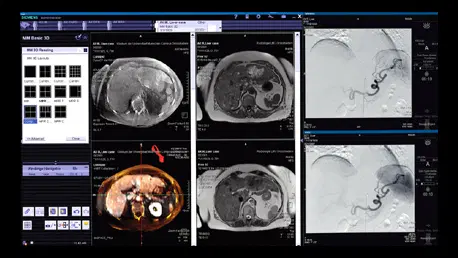

Tomógrafo CT 128 detectores para guía en tiempo real

Barridos rápidos y reconstrucciones volumétricas que permiten guía precisa de agujas y catéteres durante cada procedimiento.

Syngo: navegación y post-procesamiento

Herramientas de planificación y navegación para optimizar rutas de acceso y confirmar posicionamiento durante intervenciones.